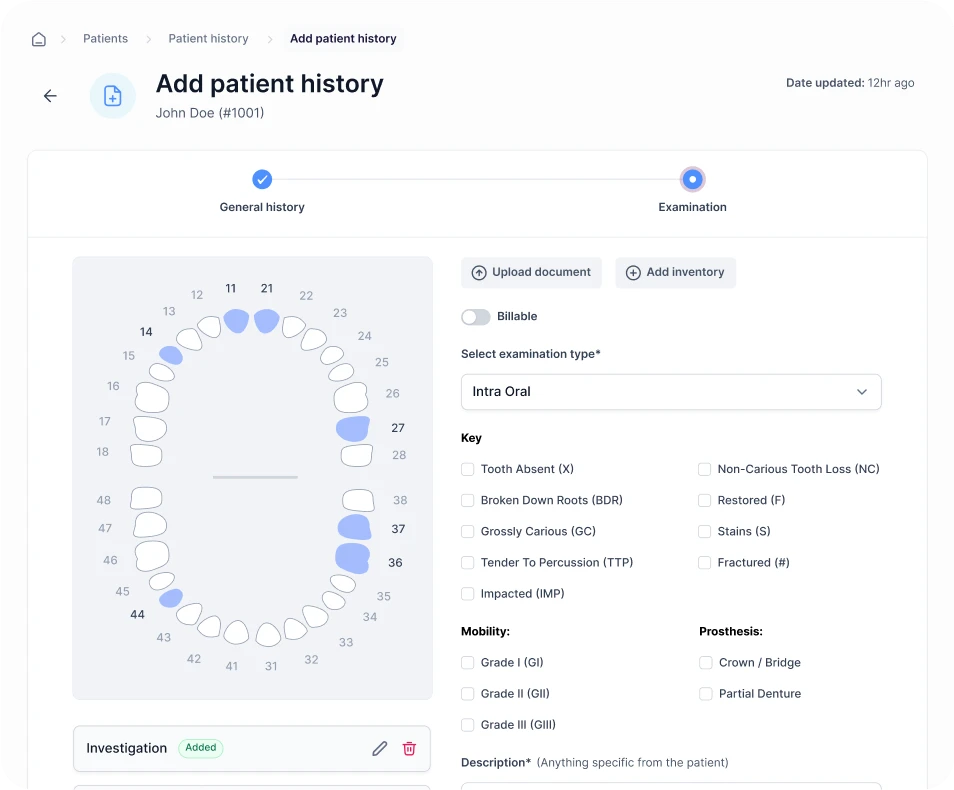

Streamline Your Workflow

Easily manage your clinic with a centralized system that automates tasks, updates schedules, and provides insights, so you can focus on patient care.

How DoxOptima Helps You

DoxOptima streamlines clinic operations with automated workflows, intuitive tools, and real-time insights, simplifying appointments, patient records, staff management, and finances for enhanced efficiency